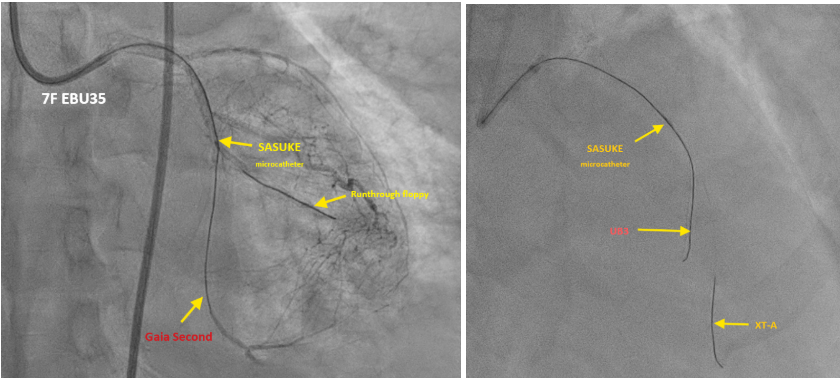

This time Left coronary angiography showed progression of LAD lesion (99% stenosis to total occlusion). We used Runthrough floppy to OM1 branch , then advanced Sasuke with XT-A via runthrough floppy for better support. For failure of passing through LCX distal lesion, we exchange XT-A to Gaia 2. Lesion was then crossed successfully then dilated with small balloons gradually (1.0 mm then 2.0 mm). We then confirmed with IVUS and showed the wire was in the true lumen.